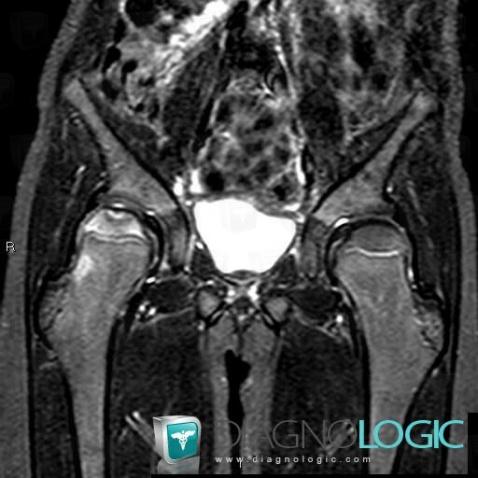

Ostéochondrite primitive-hanche, Fémur -supérieur, IRM

Voici les informations spécifiques à l'image clé ci dessus:

- Diagnostic Ostéochondrite primitive de hanche (lié à Ostéonécrose), Localisation(s) Fémur - 1/3 supérieur, comportant les gammes Ostéolyse épiphysaire